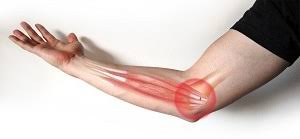

Teniszkönyök / golfkönyök (Lateral/medial epicondylitis)

A teniszkönyök, a könyök- és csukló-izület mozgatásakor jelentkező heves fájdalommal járó elváltozás a könyök külső területén. A fájdalom jellemzően az alkar külső felszínén elhelyezkedő a csukló és az ujjak nyújtásában közreműködő izmok irányába sugárzik, jellemzője a kéz szorítóerejének csökkenése, hirtelen jelentkező készsúrás szerű fájdalom. A kéz ügyetlenné válik, a beteg sokszor banális mozdulatokra is elejt tárgyakat.

A betegség oka a felkar könyök felőli végének az un. lateralis epicondylus területének csonthártya izgalma, illetve gyulladása. A gyulladást túlterhelés, fizikai munka váltja ki.

A golfkönyök a könyökizület belső felszínén, a csukló és kéz ujjak hajlító inainak tapadásánál kialakuló elváltozás, melynek oka és tünetei a teniszkönyökére hasonlítanak.

A kezelés első lépése a tehermentesítés, ami minden esetben jelentős időráfordítást, sok esetben munkából, szabadidős és sporttevékenységtől való távolmaradást is jelent.

A kezelés következő lépése az un. konzervatív kezelés, helyi hűtés, krémek alkalmazása, fizikoterápia, szájon át adott gyógyszerek. Újabban eredményesen alkalmazzuk ezen betegségek kezelésére a lökéshullám és lézer terápiát.

Harmadik lépésben helyileg adott injekciók javíthatnak a tüneteken, ez lehet steroid jellegű gyógyszer adása, de legújabban alkalmazható a saját vérből nyert un. thrombocytában dús plazma befecskendezése is, melynek során a szervezet saját védekező mechanizmusait használjuk fel a kezelés során.

A mennyiben a folyamat nem javul, vagy ismétlődik, műtéti megoldásre van szükség.